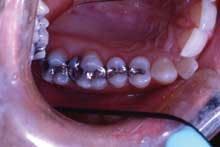

This patient is typical of our patients. She requested to have all the work in this quadrant completed at one time. The final result is a quadrant of posterior restorations that will last a long time and has improved the function and aesthetics of her teeth (Figure 2).

The benefit to the practice is important as well. We are able to work more efficiently on three or four teeth all at once than if we gave in to the "crown of the year" club mentality that we dentists help perpetuate in our patients. Also, we all know that the quality of the restorations is just a little bit better when they are all done at once - we don't "nick" the adjacent tooth while prepping; the laboratory technician has the ability to create correct and accurate proximal contacts and emergence angles; the lab technician also has the ability to help us correct or refine the patient's occlusion at this time.